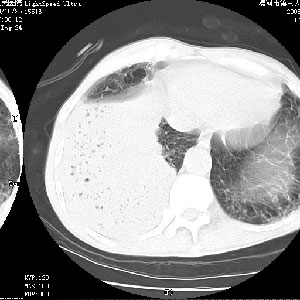

m 老年 发烧、呼吸困难,慢支、肺气肿多年;记的那次是下午大概17:38做的,晚上窒息死亡。

当时我怀疑:1、阻塞性肺不张早期 2、肺脓肿早期,望老师们发表意见

1、右侧脓胸;2、copd;

3、细支气管肺泡癌可以排除,病变以斜裂为界,呈大片状高密度影,内可见多发小气泡,表明有产气杆菌感染所致,内无明显的支气管“枯树枝征”表现,再结合其临床改变(细支气管肺泡癌临表表现重、影像表现轻)所以不符合细支气管肺泡癌(炎症型)的改变。

考虑为右肺下叶支气管痰栓形成并阻塞性肺不张及肺炎。

按肺叶分布,考虑肺不张

右下肺实变,内有弥漫分面小气泡而无支气管征,叶间裂前移,呈臌大之形,而无收缩之状,兼纵隔稍左行移,故。不支持不张,倒支持大叶肺叶,如楼上所说,小气泡不象残留之肺,不可以考虑产气菌感染吗。

阻塞性肺炎,肺脓肿形成。依据,右下支气管不通,大片实变形内可见小气泡。不支持肺不张。

右下肺阻塞性炎症,内见多发气体影,以肺叶分布.不支持不张.